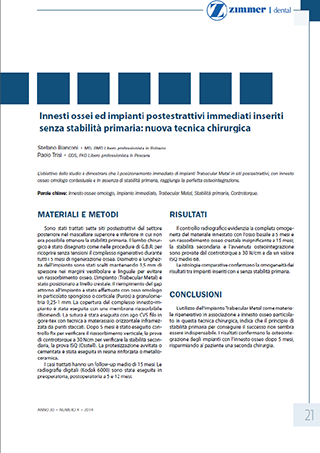

Die Studie, „Knochentransplantation und ohne Primarstabilität sofort eingefügte Implantate: neue Operationstechnik“ weist auf konkreter Weise nach, dass ein Trabecular MetalTM Implantat – durch eine besondere, aus Tantal ausgezeichnete poröse Struktur, welche mit der Substantia spongiosa vergleichbar ist und den Nachwuchs der Knochen, sowie dessen Integration mit dem Metall, fördert – eine perfekte Osseointegration ermöglicht, auch mangels der Primärstabilität (ohne dass der Implantat an den Knochen angeschraubt wird). Voraussetzung für die Erzielung eines guten Ergebnisses, ist dass dieses Implantat sofort nach der Extraktion eines Zahnes eingefügt wird, zugleich mit einem homologen (menschlichen) Knochen als Stütze. Unter Osseointegration versteht man eine starke und dauerhafte Bindung zwischen Knochen und Metall.